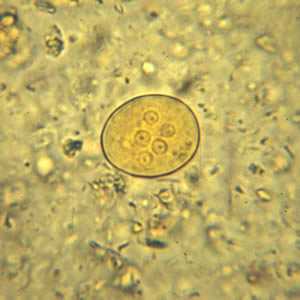

Iodamoeba buetschlii cysts in concentrated wet mounts.

Figure A: Cyst of I. buetschlii in an unstained concentrated wet mount. In these cysts, the glycogen vacuole can be seen as a large, oval refractile body.

Figure B: Cyst of I. buetschlii in an unstained concentrated wet mount. In these cysts, the glycogen vacuole can be seen as a large, oval refractile body.

Figure C: Cyst of I. buetschlii from the same specimen as seen in Figures A and B, but stained with iodine. In this cyst, the glycogen vacuole is more-easily observed as a dark-staining mass in the cyst.

Figure D: Cyst of I. buetschlii from the same specimen as seen in Figures A and B, but stained with iodine. In this cyst, the glycogen vacuole is more-easily observed as a dark-staining mass in the cyst.